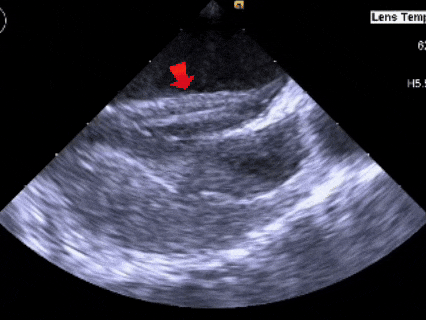

术后1个月随访

超声所见:

1、内脏正位,心房正位,心室右袢,各房室内径正常。房间隔可见封堵器回声,未见分流。右肺静脉流速0.59m/s,上腔静脉流速0.53m/s。

ASD封堵术后,未见分流

术前超声显示(分型)继发孔型房间隔缺损合并膨出瘤,房间隔中部局部呈瘤样向右房膨出范围约11×19mm,房间隔中部回声中断约11×9mm。术中超声复测膨出瘤基底宽19.61mm,深7.00mm,房间隔总长44.22mm,缺损大小14.80mm。结合患者需求,综合考量选择BDASD-II 24封堵器,配16F鞘管施行介入封堵。随后通过TEE精确引导,术者成功完成了鞘管及封堵器的输送、定位与释放,并对封堵效果进行了仔细评估,确保了手术的成功。术后即刻TEE显示封堵效果确切,无残余分流及严重并发症发生。术后1个月随访时房间隔可见封堵器回声,未见分流。其长期疗效及降解特性有待进一步随访观察。